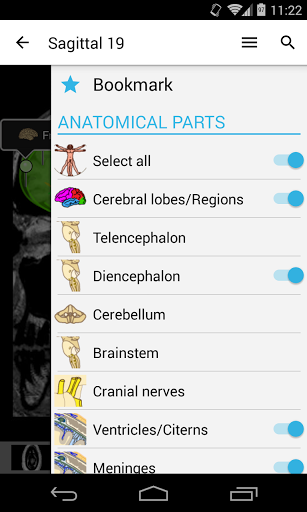

*Improved detail view of anatomical parts for easier identification in images of the current and other modules.

*Find your anatomical parts more easily thanks to the new, more intuitive and powerful search feature